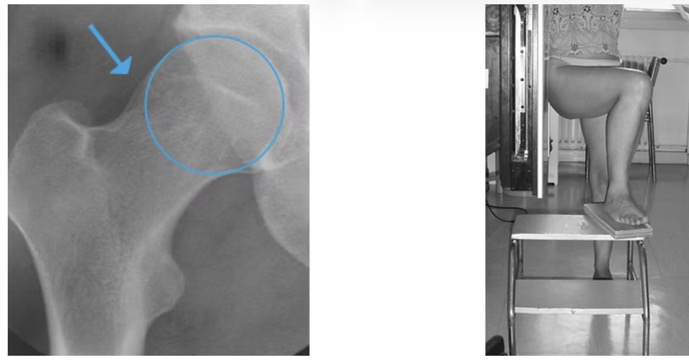

- 1. Le conflit de type CAM (a): excès d'os de la tête et le col fémoral => pas parfaitement ronds